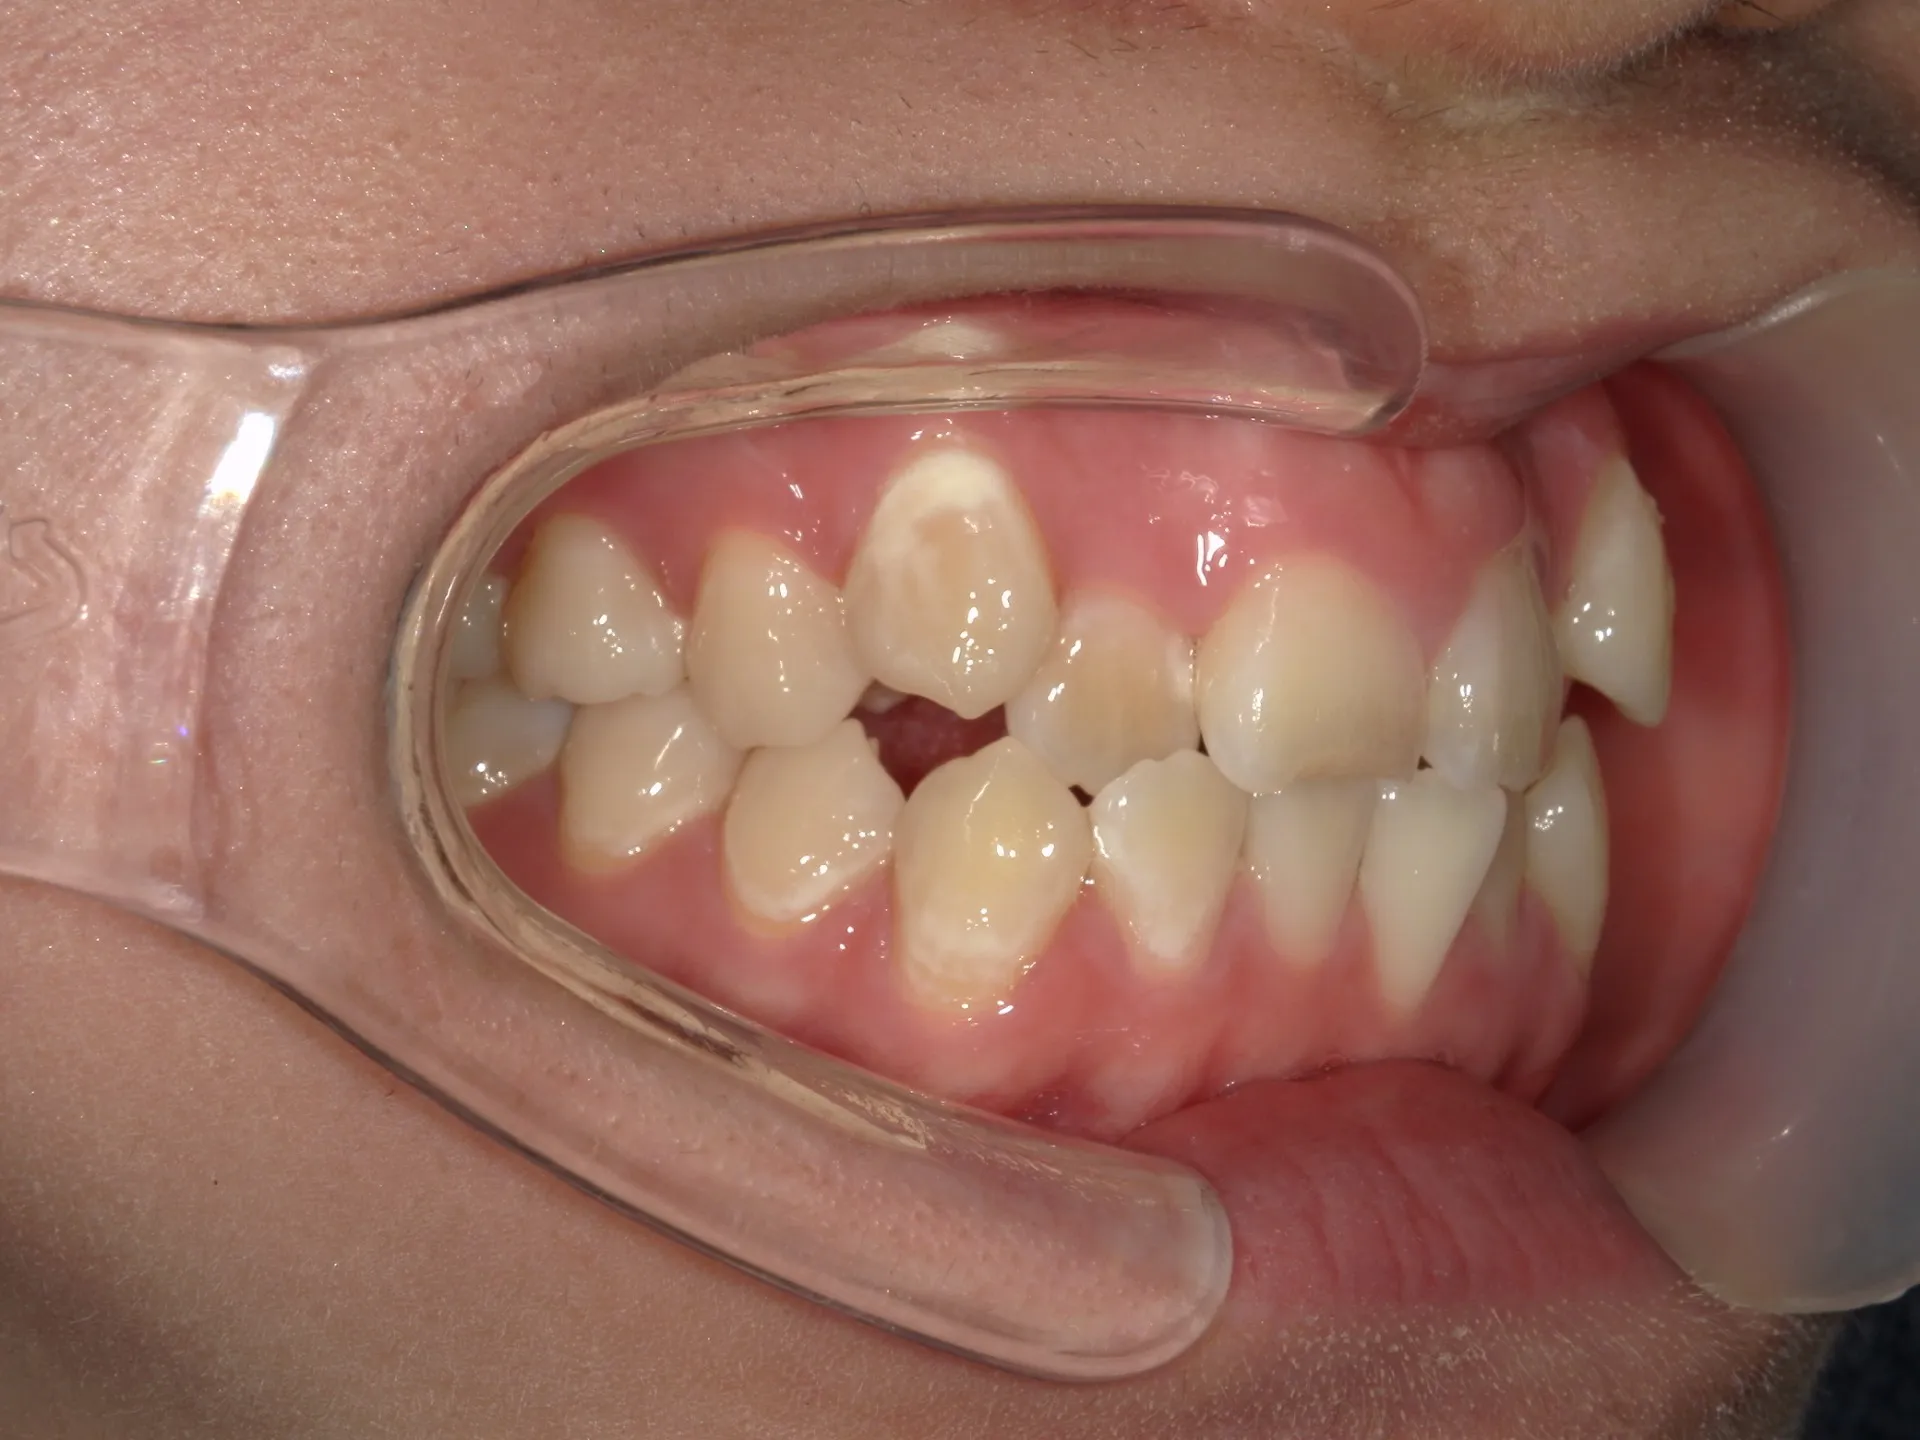

今回はマウスピース矯正で治療した八重歯の矯正についてご紹介いたします。

どこまでが軽度でどこまでが中等度のガタツキなのかにもよりますが、治療前の歯並びであれば患者さんの協力も当然必要ですが、マウスピース矯正でも十分治療できることが分かります。